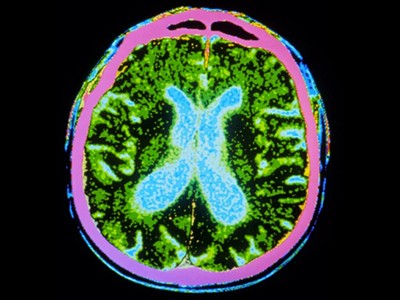

截至去年12月,共有83種源自多能干細(xì)胞的產(chǎn)品正在進(jìn)行115項(xiàng)臨床試驗(yàn)。帕金森病的治療方法比任何其他中樞神經(jīng)系統(tǒng)疾病的治療方法都處于更先進(jìn)的發(fā)展階段。帕金森病的特征是釋放神經(jīng)遞質(zhì)分子多巴胺的神經(jīng)元逐漸喪失。帕金森病相關(guān)的運(yùn)動(dòng)癥狀,例如肌肉僵硬、運(yùn)動(dòng)遲緩、震顫和步態(tài)障礙,都是由中腦黑質(zhì)區(qū)域神經(jīng)元的耗竭引起的。

帕金森病是由于大腦中釋放多巴胺(多巴胺能)神經(jīng)元逐漸喪失所致。Sawamoto 等人1和 Tabar 等人2進(jìn)行了一項(xiàng)基于干細(xì)胞治療的臨床試驗(yàn)。兩個(gè)團(tuán)隊(duì)都使用了臨床級多能干細(xì)胞來補(bǔ)充多巴胺能神經(jīng)元,這種細(xì)胞可以無限分裂并分化為任何細(xì)胞類型。Sawamoto等人使用了源自健康成年捐贈(zèng)者細(xì)胞的誘導(dǎo)多能干細(xì)胞系,而Tabar等人使用了源自早期胚胎的人類胚胎干細(xì)胞系。干細(xì)胞經(jīng)過培養(yǎng),形成多巴胺能神經(jīng)元祖細(xì)胞。這些細(xì)胞被移植到稱為殼核的大腦區(qū)域,殼核與尾狀核一起形成紋狀體。紋狀體與黑質(zhì)相連,而黑質(zhì)是多巴胺能神經(jīng)元損失最為嚴(yán)重的部位。早期(I/II期)臨床試驗(yàn)主要證實(shí)了該療法的安全性,同時(shí)也表明其在改善癥狀方面具有一定有效性。